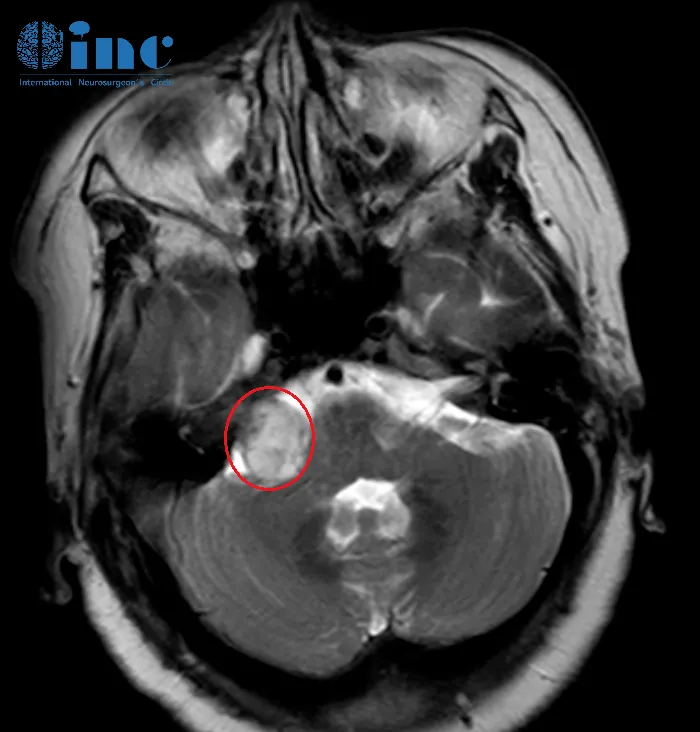

2022年10月14日,齊奶奶常規(guī)進(jìn)行腦積水治療后影像檢查,沒(méi)想到卻聽(tīng)到了一個(gè)讓一家人再次陷入恐慌消息,腫瘤目前大小尺寸為32mmX22mmX26mm,已經(jīng)超過(guò)了3cm大??!

早在2018年,齊奶奶就出現(xiàn)了右耳的聽(tīng)力障礙,最初以為是年紀(jì)大了耳背,但是兩年后,齊奶奶開(kāi)始出現(xiàn)走路不穩(wěn),容易走偏,下肢無(wú)力,在行走剛開(kāi)始時(shí)情況正常,行走十分鐘左右感到吃力,此時(shí)會(huì)不由自主地加快腳步,如果沒(méi)有人攙扶,容易跌倒。白天大小便有時(shí)失禁。一家人帶齊奶奶就醫(yī)檢查,2021年5月和10月兩次進(jìn)行MRI檢查,提示右側(cè)聽(tīng)神經(jīng)瘤,腦積水,腫瘤尺寸20mmX15mmX19mm。這時(shí)一家人才反應(yīng)過(guò)來(lái)原來(lái)3年前的右耳聽(tīng)力障礙很有可能就是聽(tīng)神經(jīng)瘤已經(jīng)在作祟。而后越演越烈的步態(tài)不穩(wěn)、下肢無(wú)力等則是由于腦積水導(dǎo)致的癥狀。